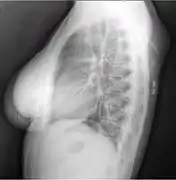

Lipomas are rarely life-threatening, and the common subcutaneous lipomas are not a serious condition. Lipomas growing in internal organs can be more dangerous; for example, lipomas in the gastrointestinal tract can cause bleeding, ulceration, and painful obstructions (so-called "malignant by location", despite being a benign growth histologically).[29][30] Malignant transformation of lipomas into liposarcomas is very rare, and most liposarcomas are not produced from pre-existing benign lesions.[25] A few cases of malignant transformation have been described for bone and kidney lipomas,[31][32] but it is possible that these few reported cases were well-differentiated liposarcomas in which the subtle malignant characteristics were missed when the tumor was first examined.[33] Deep lipomas have a greater tendency to recur than superficial lipomas because complete surgical removal of deep lipomas is not always possible.[33][34]

The presence of multiple lipomas, lipomatosis, is more commonly encountered in men. Some superficial lipomas can extend into deep fascia and may complicate excision. Liposarcoma is found in 1% of lipomas and is more likely to occur in lesions of the lower extremities, shoulders, and retroperitoneal areas. Other risk factors for liposarcoma include large size (>5 cm), associated with calcification, rapid growth, and/or invasion into nearby structures or through fascia into muscle tissue.[35]